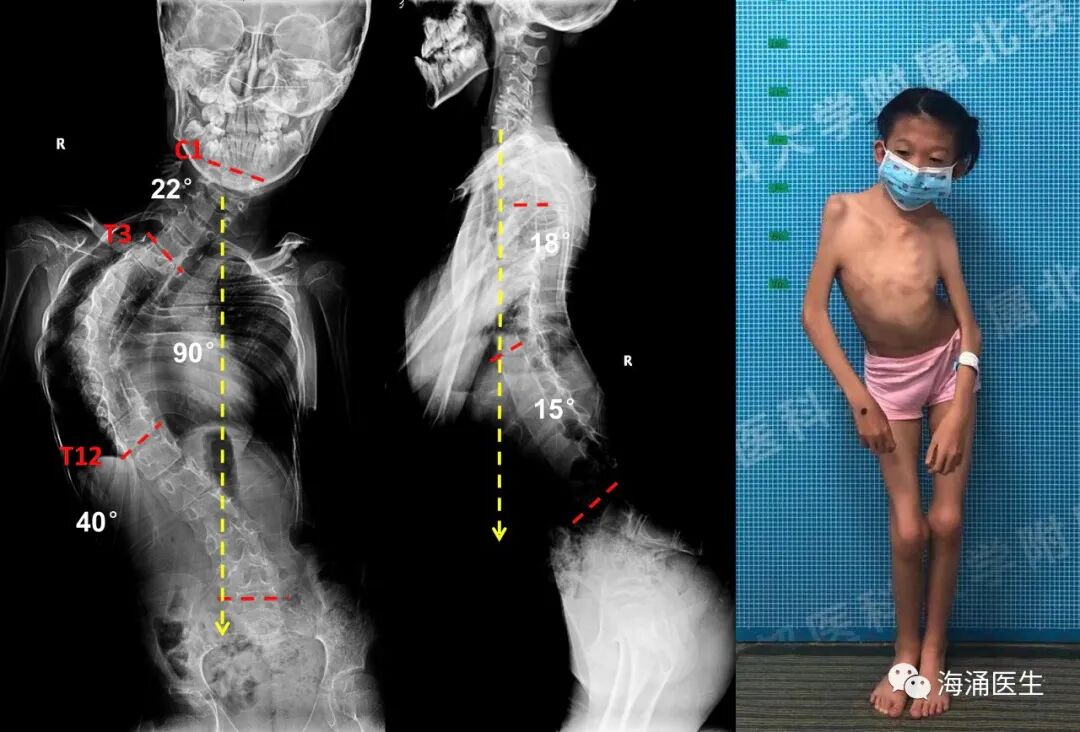

尤其需要指出的是,本人作为近 30 年专门从事脊柱侧弯诊断和治疗的脊柱外科医生,很遗憾的告诉大家,上述罕见病中导致脊柱侧弯的不在少数,如马凡氏综合征、多关节挛缩症、成骨不全症、多发性骨骺发育不全症等,更是有相当高的发生率。

这一类脊柱侧弯有这样的特点,发生早,发展快,弯曲僵硬且严重,还往往合并骨质不良,全身状况不佳,甚至不能行走。而且这一类罕见病往往缺乏针对病因的治疗方法,对脊柱侧弯的治疗也往往是针对原发疾病结果的治疗。因此在治疗上有很多未知和挑战。

术前牵引和呼吸功能锻炼

正在住院治疗的患者

对于这些罕见病及复杂综合征导致的脊柱畸形,国内外文献报道例数少,治疗经验有限,且该类患者多全身脏器受累,病情复杂,部分病情较重,围手术期风险高。针对每一位这样的罕见患者,需要全面评估并实施个体化的治疗方案。

我们的团队,近年来致力于各种脊柱侧弯的诊断、治疗和研究,对上述罕见病导致的脊柱侧弯也积累了较丰富的经验。个体化的治疗方案以及围手术期多学科 MDT 的实施,使患者的治疗效果和安全性得到了显著提高。